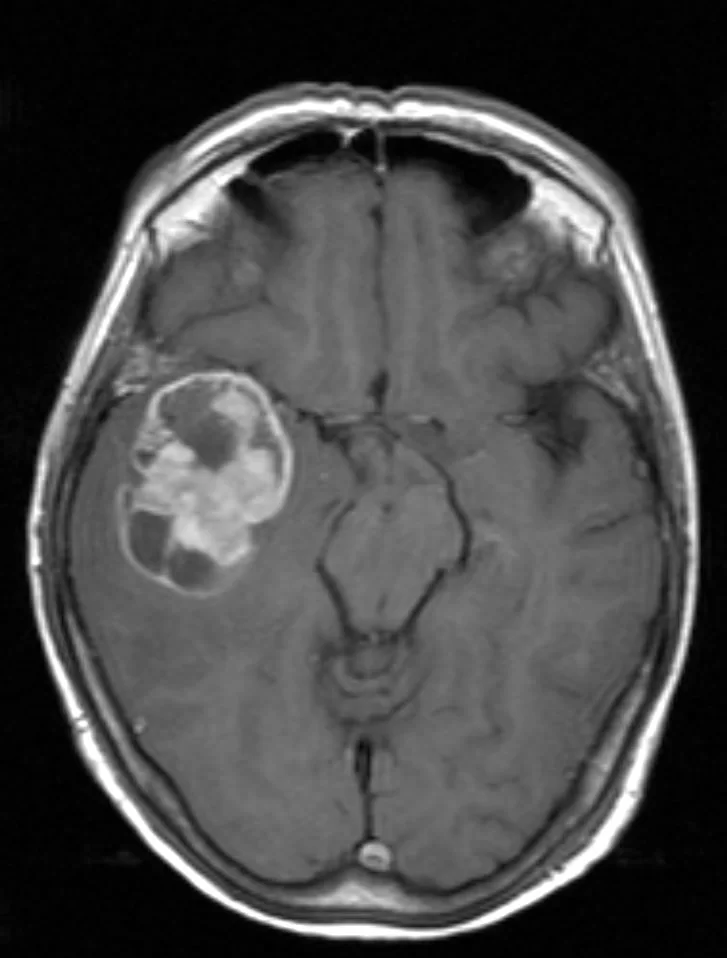

Γλοιοβλάστωμα Δεξιά Κροταφικά

Ασθενής γυναίκα, 67 ετών παρουσίασε επιληπτική κρίση. Η μαγνητική τομογραφία ανέδειξε ευμεγέθη χωροκατακτητική εξεργασία δεξιά κροταφικά με σημαντικό περιεστιακό οίδημα, ύποπτη για κακόηθες γλοίωμα. Διενεργήθη δεξιά